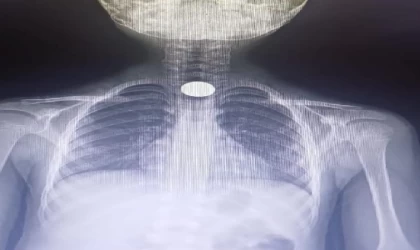

Güvenlik